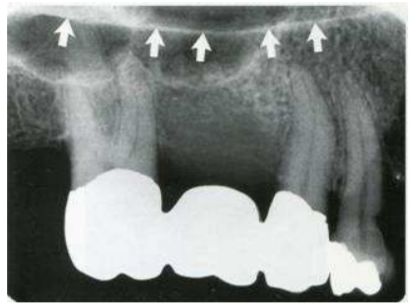

62.附圖箭頭所指,1與2之影像分別為: (A)1為border of maxillary sinus,2為zygomatic process (B)1為floor of nasal fossa,2為zygomatic process (C)1為zygomatic process,2為sinus septum (D)1為floor of nasal fossa,2為border of maxillary sinus

63.附圖根尖X光片中,白色箭頭所指為何種構造? (A)anterior floor of the maxillary sinus (B)floor of the nasal aperture (C)cortical bone of the hard palate (D)posterior extension of nasal septum